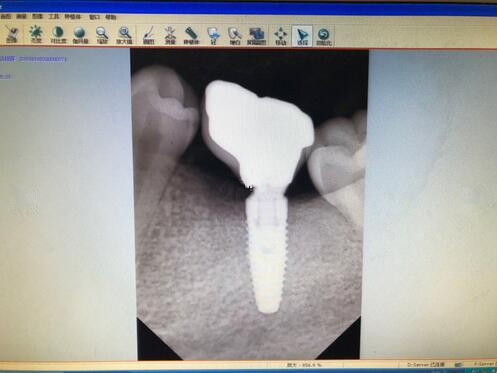

廣州牙齒整形種植牙果圖

在手術的過程中打了麻藥,而且醫(yī)生也一直在詢問有沒有什么不舒服的感覺,如果有不舒服,一定要第一時間告訴他,所以說還是比較舒適的整個過程。我的牙齒一共壞了四顆,所以說手術的時間還是比較久的,大概是用了將近三個小時的時間才完全結束,在這三個小時里面,口腔一直長著,還是覺得有一些口干的。

現(xiàn)在牙齒已經(jīng)恢復的相當?shù)暮昧?,大家可以看到這幾顆種植牙,看起來比之前的牙齒都更加好看了呢,而且更加的潔白也結實了不少,之前不敢吃的一些食物,現(xiàn)在都可以吃了。